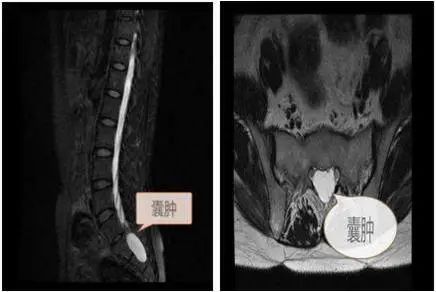

骶管囊肿,顾名思义就是位于骶管内的囊性肿物,其实不是单一类型囊肿,到目前为止至少包括四种类型。囊肿多为单发,少数为多发,发病部位以骶2及骶3最为多见。绝大多数没有临床症状,只是在影像学检查时无意中发现。自从核磁共振检查在临床上广泛应用以来,骶管囊肿的发现率愈来愈高,引起患者极大的顾虑。